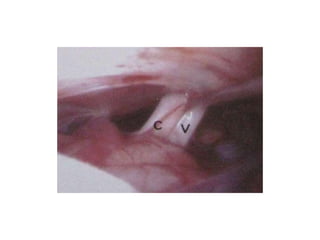

The space between a & oc is Lamina terminalis

Neuroendoscopic view of the third ventricle floor-----Infundibular recess (i), optic chiasm (oc)

and a prominent anterior commissure (a) are seen anterior to the opaque and narrow tuber cinereum (t). B

Neuroendoscopic view of the third ventricle floor in another myelomeningocele patient. A non-transparent

tuber cinereum (t) and a dilated infundibular recess (i) are seen anterior to the mamillary bodies (m). Note to

the vascular structure of the third ventricle floor. cNeuroendoscopic view showing a steep third ventricle

floor in a myelomeningocele patient. A narrow tuber cinereum (t) is visible just anterior to the mamillary

bodies (m). dNeuroendoscopic view through a very narrow prepontine cistern. Note the close proximity of

the basillary artery (ba) and clivus (cl)